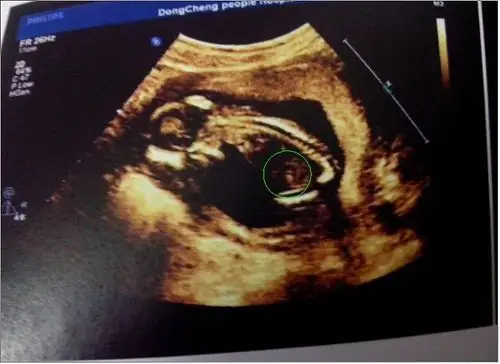

b超图有"凸出的东西",那是男孩的标志,这是男孩女孩最突出的**特征

问答 怀孕期 七宝qibao831孕23周2天2017-05-06 推荐回答